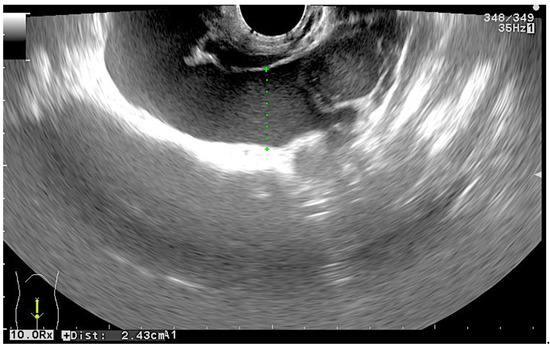

2. Case Presentation